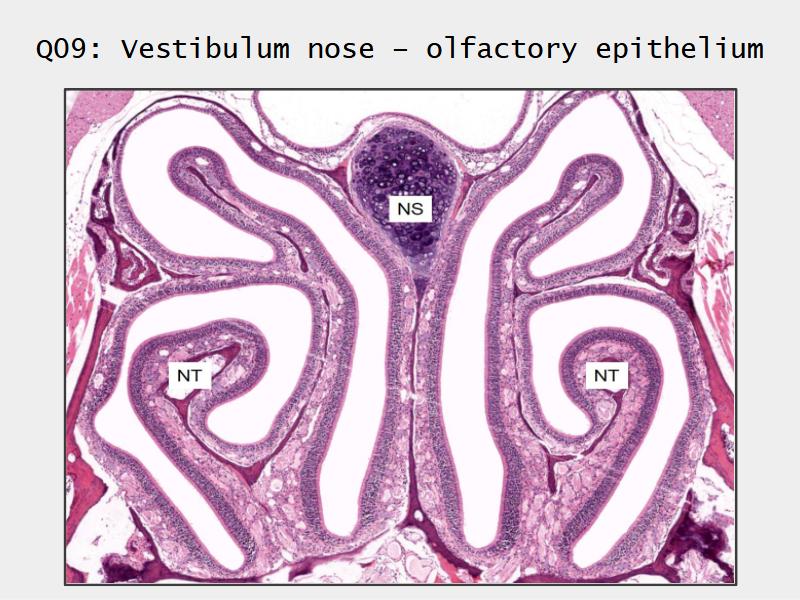

Slides: Respiratory System

- Slide 71: Nostril

- Slide 108: Olfactory epithelium

Olfactory epithelium

Function of the nasal cavity?

Function of the nasal cavity?

- Warm

- Moisture

- Filter

- Smell